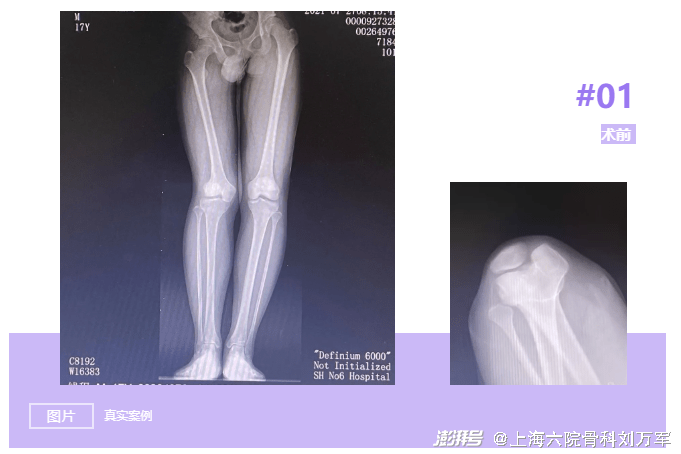

小钱今年17岁,在5年前因车祸导致右膝关节髌骨骨折,在当地医院进行了“石膏固定”治疗。后期康复锻炼时出现右膝关节活动障碍,膝关节疼痛,同时伴有膝关节屈曲受限,经药物等保守无效。为求进一步诊治,小钱慕名来到上海市第六人民医院就诊。门诊摄片提示:双下肢欠对称,骨盆右倾,右膝外翻,右髌骨脱位可能。门诊拟“右膝关节损伤、右髌骨脱位”收入病房。

关节外科刘万军主任针对小钱的病情,分析他多年来膝关节疼痛的原因是因为右下肢外翻畸形导致膝关节外侧间隙压力增加,软骨磨损严重,导致外侧间隙变窄、疼痛,临床表现为外侧骨性关节炎;另外髌骨脱位也导致伸膝装置的挛缩和髌骨外侧结构的挛缩。长期的疼痛和关节畸形,导致长短腿,让小钱的骨盆出现倾斜,继而会出现脊柱侧弯,高低肩等等一系列问题。

考虑患者年龄尚轻,可进行股骨远端闭合截骨术(DFO)纠正下肢力线,将膝关节负重中心内移,减少外侧间室的压力来改善症状,延缓患者关节置换的时间或者避免关节置换。